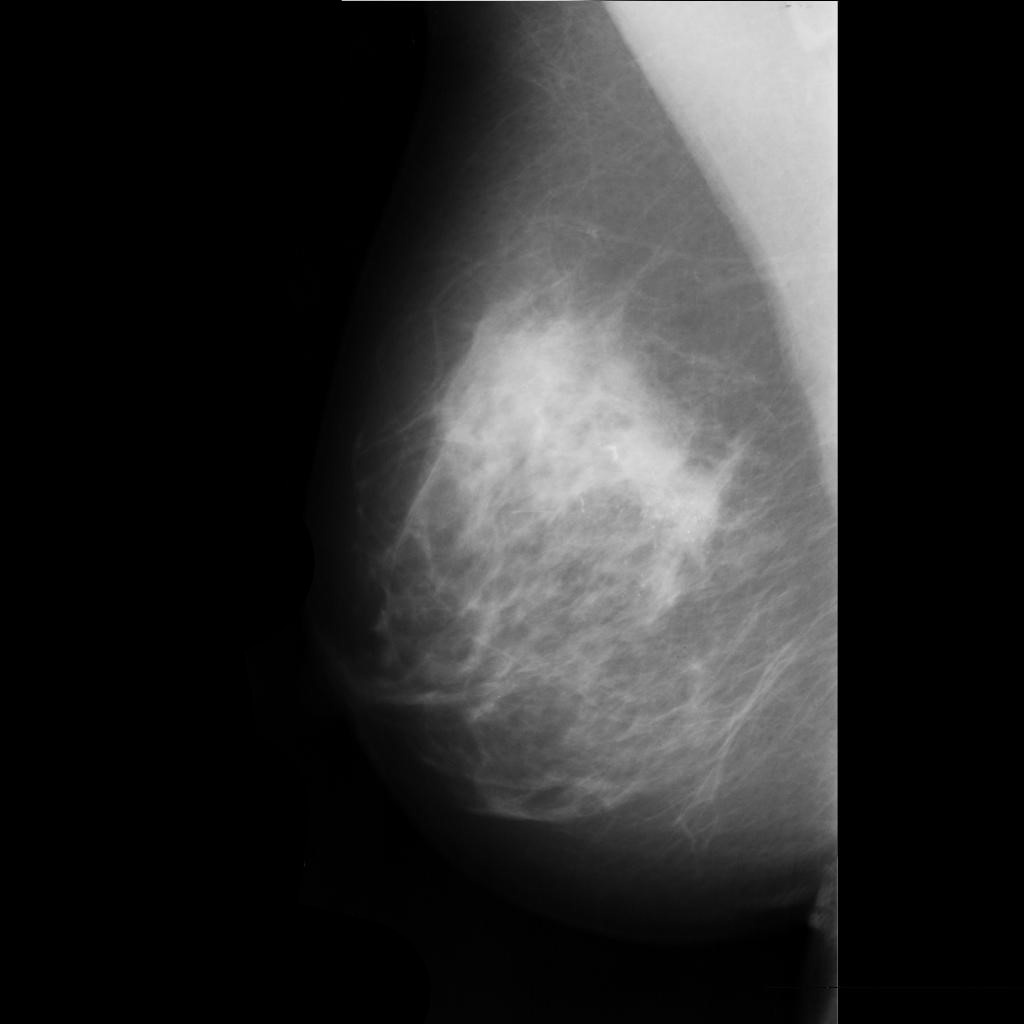

malignant